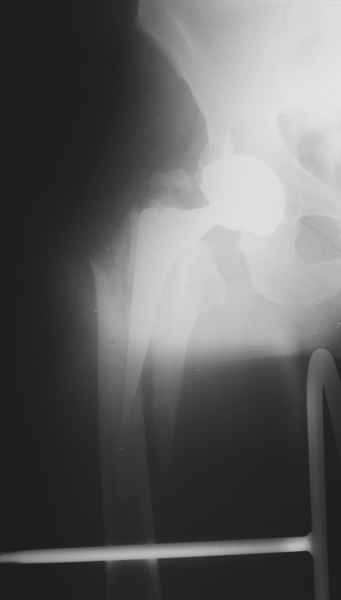

1.Остеосинтез на ножке. Мне кажется, что применительно к этому случаю малоперспективный вариант. Синтез хорош, когда можно его выполнить в малоинвазивном исполнении и достигнуть стабильности. Действительно, если ножка б/цементной фиксации после этого не будет иметь фиксации, то ревизия не будет иметь проблем. В представленном случае стабильность синтеза сомнительная, а проведение доп.иммобилизации приведет к контрактуре суставов.

Хочется показать два подобных случая, П-ка З. 72 лет и п-т Г. 80 лет. Сразу принимаю замечание, что это были ножки цементной фиксации, просто под руками не было бесцементника.